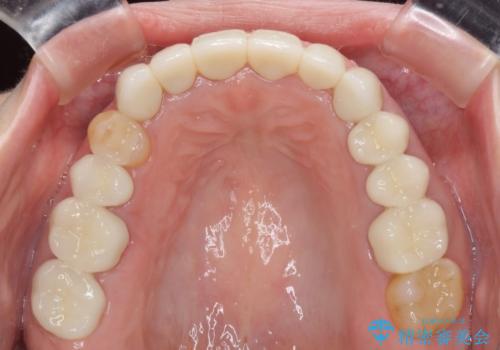

期間と費用はかかりましたが、気になっていた部分全てを改善でき、患者様には大変満足していただきました。